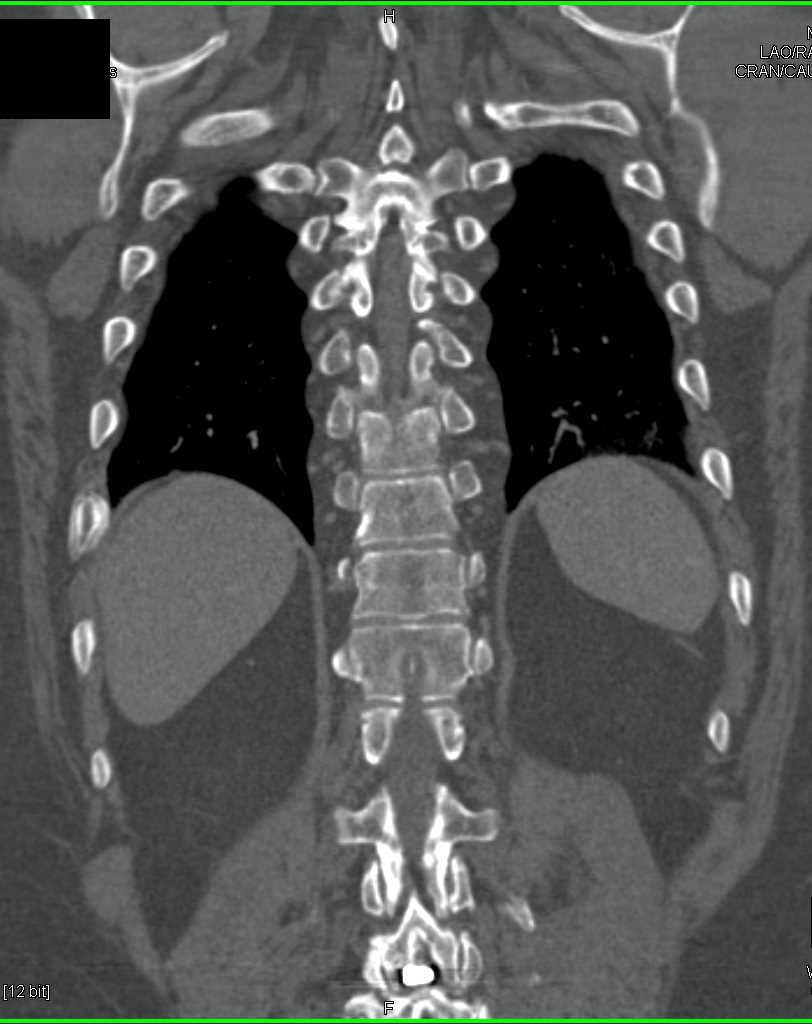

GSW Knee Without Vascular Injury with DE-CT